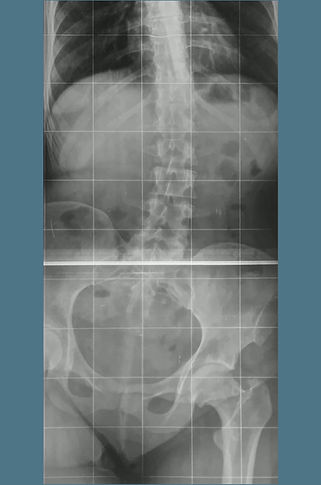

As malformações congênitas exigem abordagem individualizada, considerando idade, potencial de crescimento e função. O plano terapêutico combina fisioterapia, órteses e, quando indicado, cirurgia reconstrutiva staged. Técnicas incluem epifisiodese para controle de crescimento, alongamento ósseo gradual com fixador externo ou haste motorizada, transferências tendíneas, osteotomias direcionadas e reconstrução articular. Em deficiências longitudinais, pode-se realinhar segmentos, estabilizar o quadril/joelho/tornozelo através de técnicas de reconstrução articular como Superhip, Superknee, Superankle e otimizar o apoio plantar. O objetivo é alinhar, equalizar comprimentos e melhorar a marcha, preservando o máximo de tecido nativo e respeitando marcos de desenvolvimento.

As displasias ósseas são alterações no crescimento e na estrutura dos ossos que podem causar deformidades, encurtamento dos membros superiores e inferiores e causam limitações de função e estética. Em casos mais graves, o osso cresce torto ou enfraquecido, exigindo tratamento especializado.  O método de reconstrução óssea é a principal opção nesses casos. Ele utiliza fixadores externos, como o Ilizarov ou o TL-Hex, ou implantes internos que permitem corrigir deformidades e alongar o osso de forma gradual e segura. Após um corte controlado (corticotomia), o osso é separado milímetro a milímetro, e o corpo forma novo tecido ósseo entre as partes, recuperando o alinhamento e o comprimento natural. Um exemplo é a displasia fibrocartilaginosa focal, em que parte do osso é substituída por tecido fibrocartilaginoso, causando encurvamento progressivo e encurtamento. O tratamento com reconstrução óssea permite realinhar o membro, restaurar o comprimento e melhorar a função. O objetivo final é reestabelecer a forma, o equilíbrio, o movimento, devolvendo ao paciente melhor qualidade de vida.

A acondroplasia é a displasia mais comum e uma condição genética que causa alterações no crescimento dos ossos longos, resultando em baixa estatura e membros encurtados, mas desenvolvimento intelectual preservados. Podem ocorrer deformidades e limitação da marcha e dos membros superiores. O tratamento pode ser medicamentoso e cirúrgico, conforme a idade e a gravidade. Já existem medicamentos como o vosoritide, que atuam diretamente sobre o crescimento ósseo, estimulando o alongamento das cartilagens de crescimento e reduzindo o ritmo de deformidades em crianças. Nos casos com encurtamento mais acentuado ou deformidades já estabelecidas, o tratamento cirúrgico é o mais indicado. As opções incluem o método de reconstrução óssea com fixadores externos (como o monolateral e o hexapodal) ou o uso de hastes motorizadas de alongamento intraósseo, que permitem alongar o osso de forma controlada e discreta, sem estrutura externa visível. Ambos os métodos utilizam o princípio biológico da distração osteogênica, em que o osso é gradualmente separado após uma osteotomia, formando novo tecido ósseo. O objetivo do tratamento é melhorar a proporção corporal, corrigir deformidades, ampliar a função dos membros com maior independência e qualidade de vida.